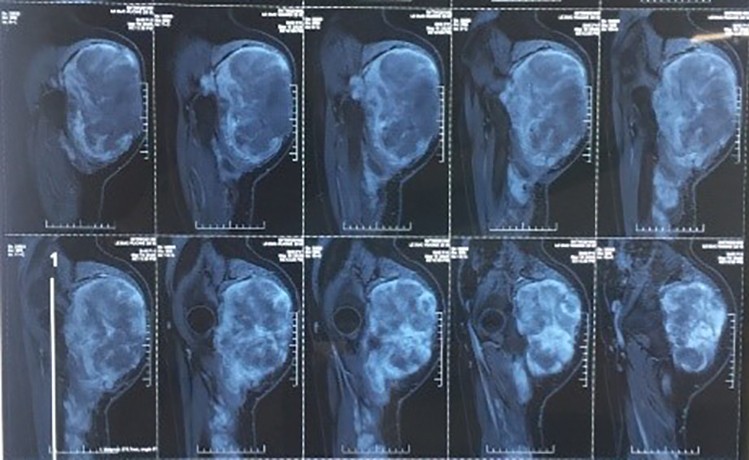

Thanh niên mang khối u to như quả bóng gần phổi

Bệnh ung thư - 22/04/2020

Bác sĩ phát hiện trong ngực nam thanh niên 24 tuổi có khối u kích cỡ lớn, chèn ép cả phổi và tĩnh mạch.